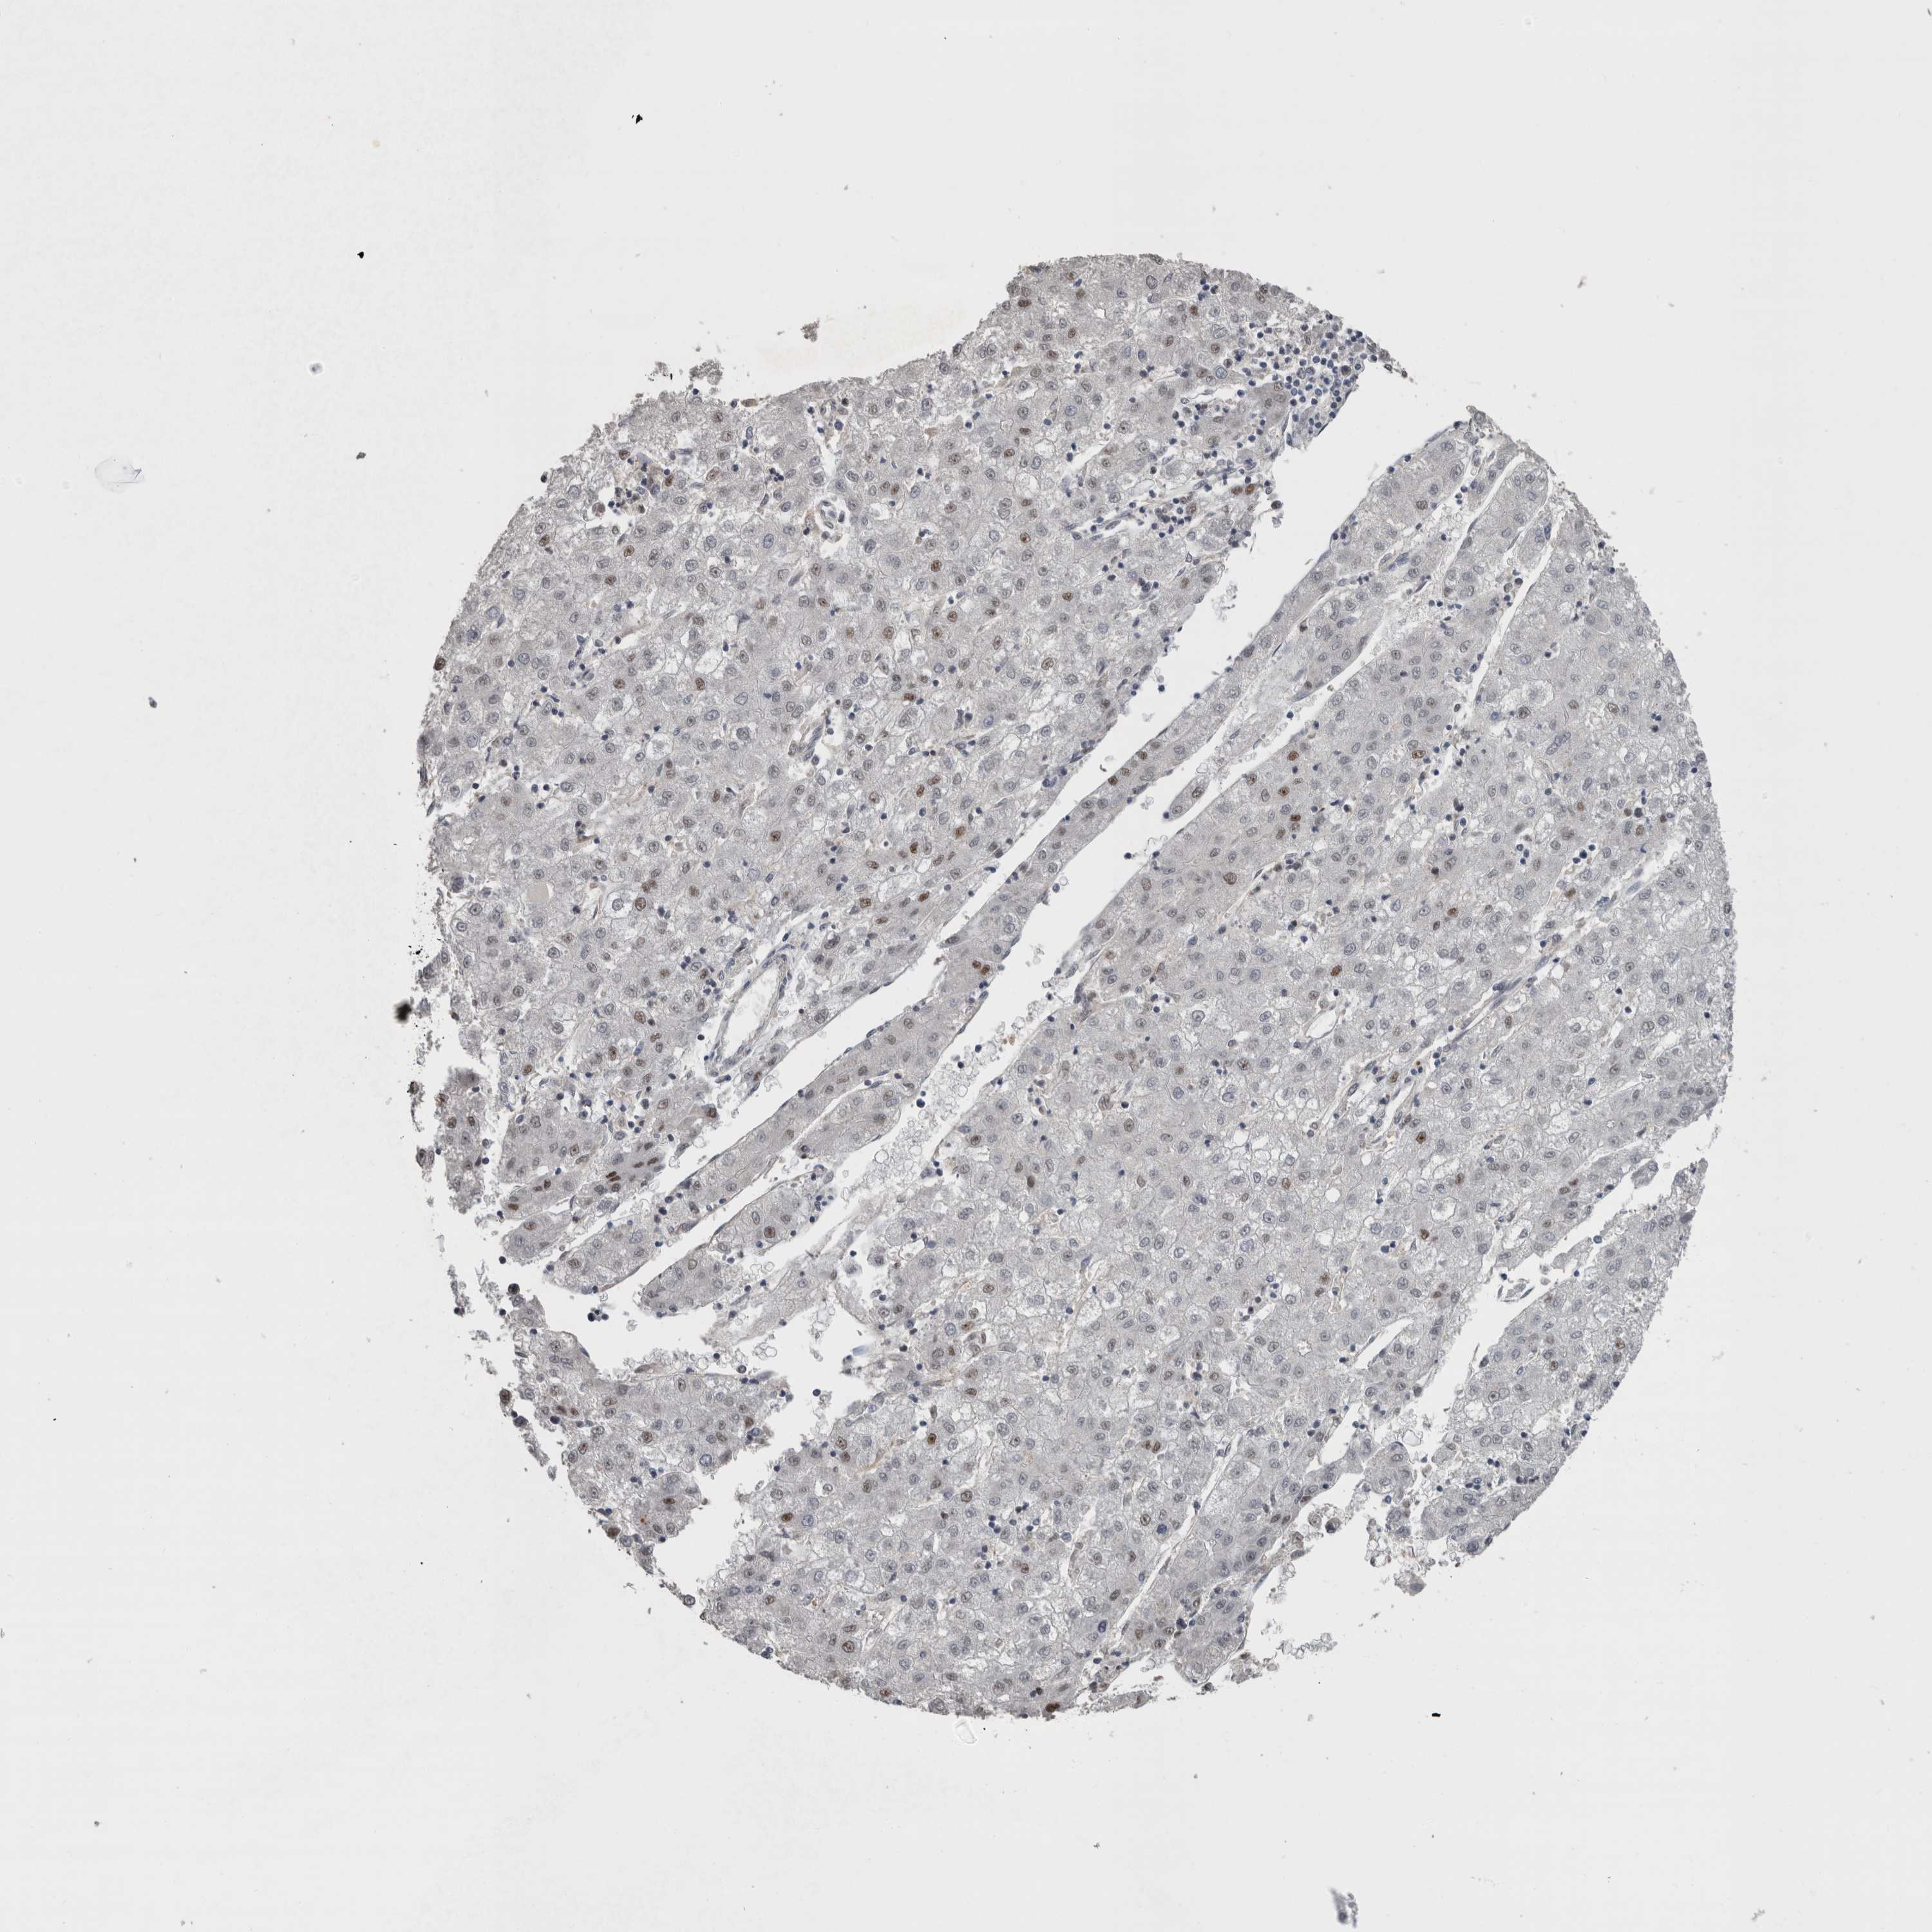

LIVER CANCER - Protein expressioni

A mouse-over function shows sample information and annotation data. Click on an image to view it in a full screen mode. Samples can be filtered based on level of antibody staining by selecting one or several of the following categories: high, medium, low and not detected. The assay and annotation is described here.

Note that samples used for immunohistochemistry by the Human Protein Atlas do not correspond to samples in the TCGA dataset.

Antibody stainingi

Antibody staining in the annotated cell types in the current human tissue is reported as not detected, low, medium, or high, based on conventional immunohistochemistry profiling in selected tissues. This score is based on the combination of the staining intensity and fraction of stained cells.

Each image is clickable and will lead to virtual microscopy that enables deeper exploration of all samples and also displays staining intensity scores, fraction scores and subcellular localization as well as patient and tissue information for each sample.

Antibody HPA026745

Staining

High

Medium

Low

Not detected

Intensity

Strong

Moderate

Weak

Negative

Quantity

>75%

75%-25%

<25%

None

Location

Nuclear

Cytoplasmic/membranous

Cytoplasmic/membranous,nuclear

Cholangiocarcinoma

Carcinoma, Hepatocellular, NOS